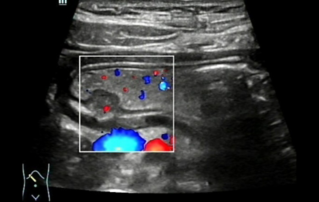

?? ?? ??? ?????(Endocavity volume convex array transducer)(DE10-3WU, Resona 7, ?????)? ??? ??? ???, ??? ?? 1/3 ?? ? ??(anterior vaginal wall)? ???? 18x14 mm ??? ?? ??(an ovoid-shaped formation) with a parietal fine suspension, ????? ??? ???? ??(non-displaced), ????,? CDI ??? ?? ?? ???? ????????. 3D ??? -? ??? ? ??(hyperechoic septa)? ?? ???? ??? ?? ??.